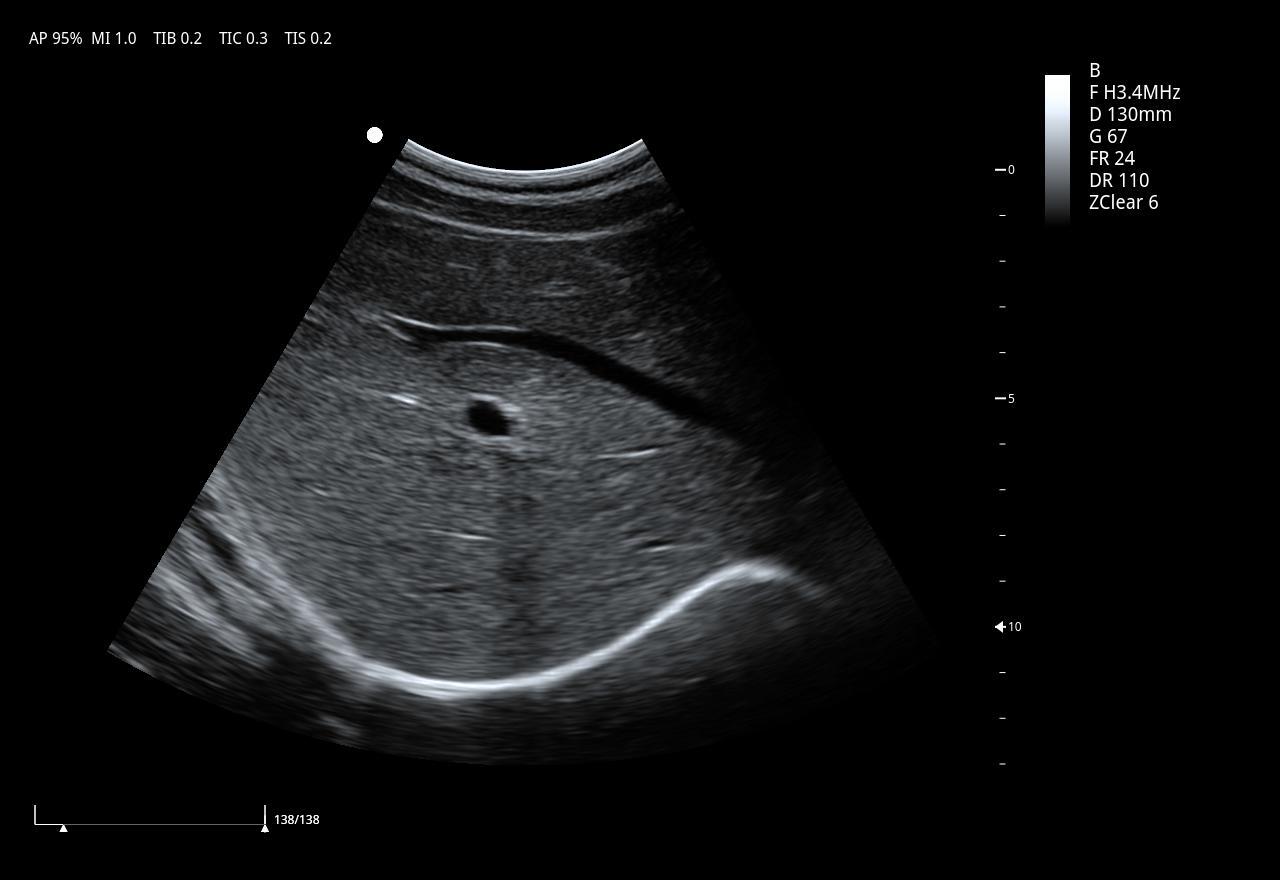

DMU27 Full Digital Color Doppler Ultrasonic Diagnostic Scanner For Human Being

1.Ergonomic Design:1) 185mm Adjustable height ofcontrolpanel2) 21.5 medical LCD monitor 3)13.3 high sensitivitytouch screen 4)Optimized control panel5)Optimized TGCArea6) 4 universal transducer connectors7)Cable Management2.Techno...

2.Technologies:

Pulse Inverse Harmonic Imaging:PIHI,PIHI reduces the distortion generated by the fundamental wave,and greatly improve the signal-to-noise ratio

Speckle Reduction Imaging:SRI technology significantly reduces the unwanted speckle,providesenhanced tissue boundary

3.Spatial Compound Imaging:SCI provides bettercontrast resolution,reduces the speckle noise and smoothes the imaging of homogeneous tissue